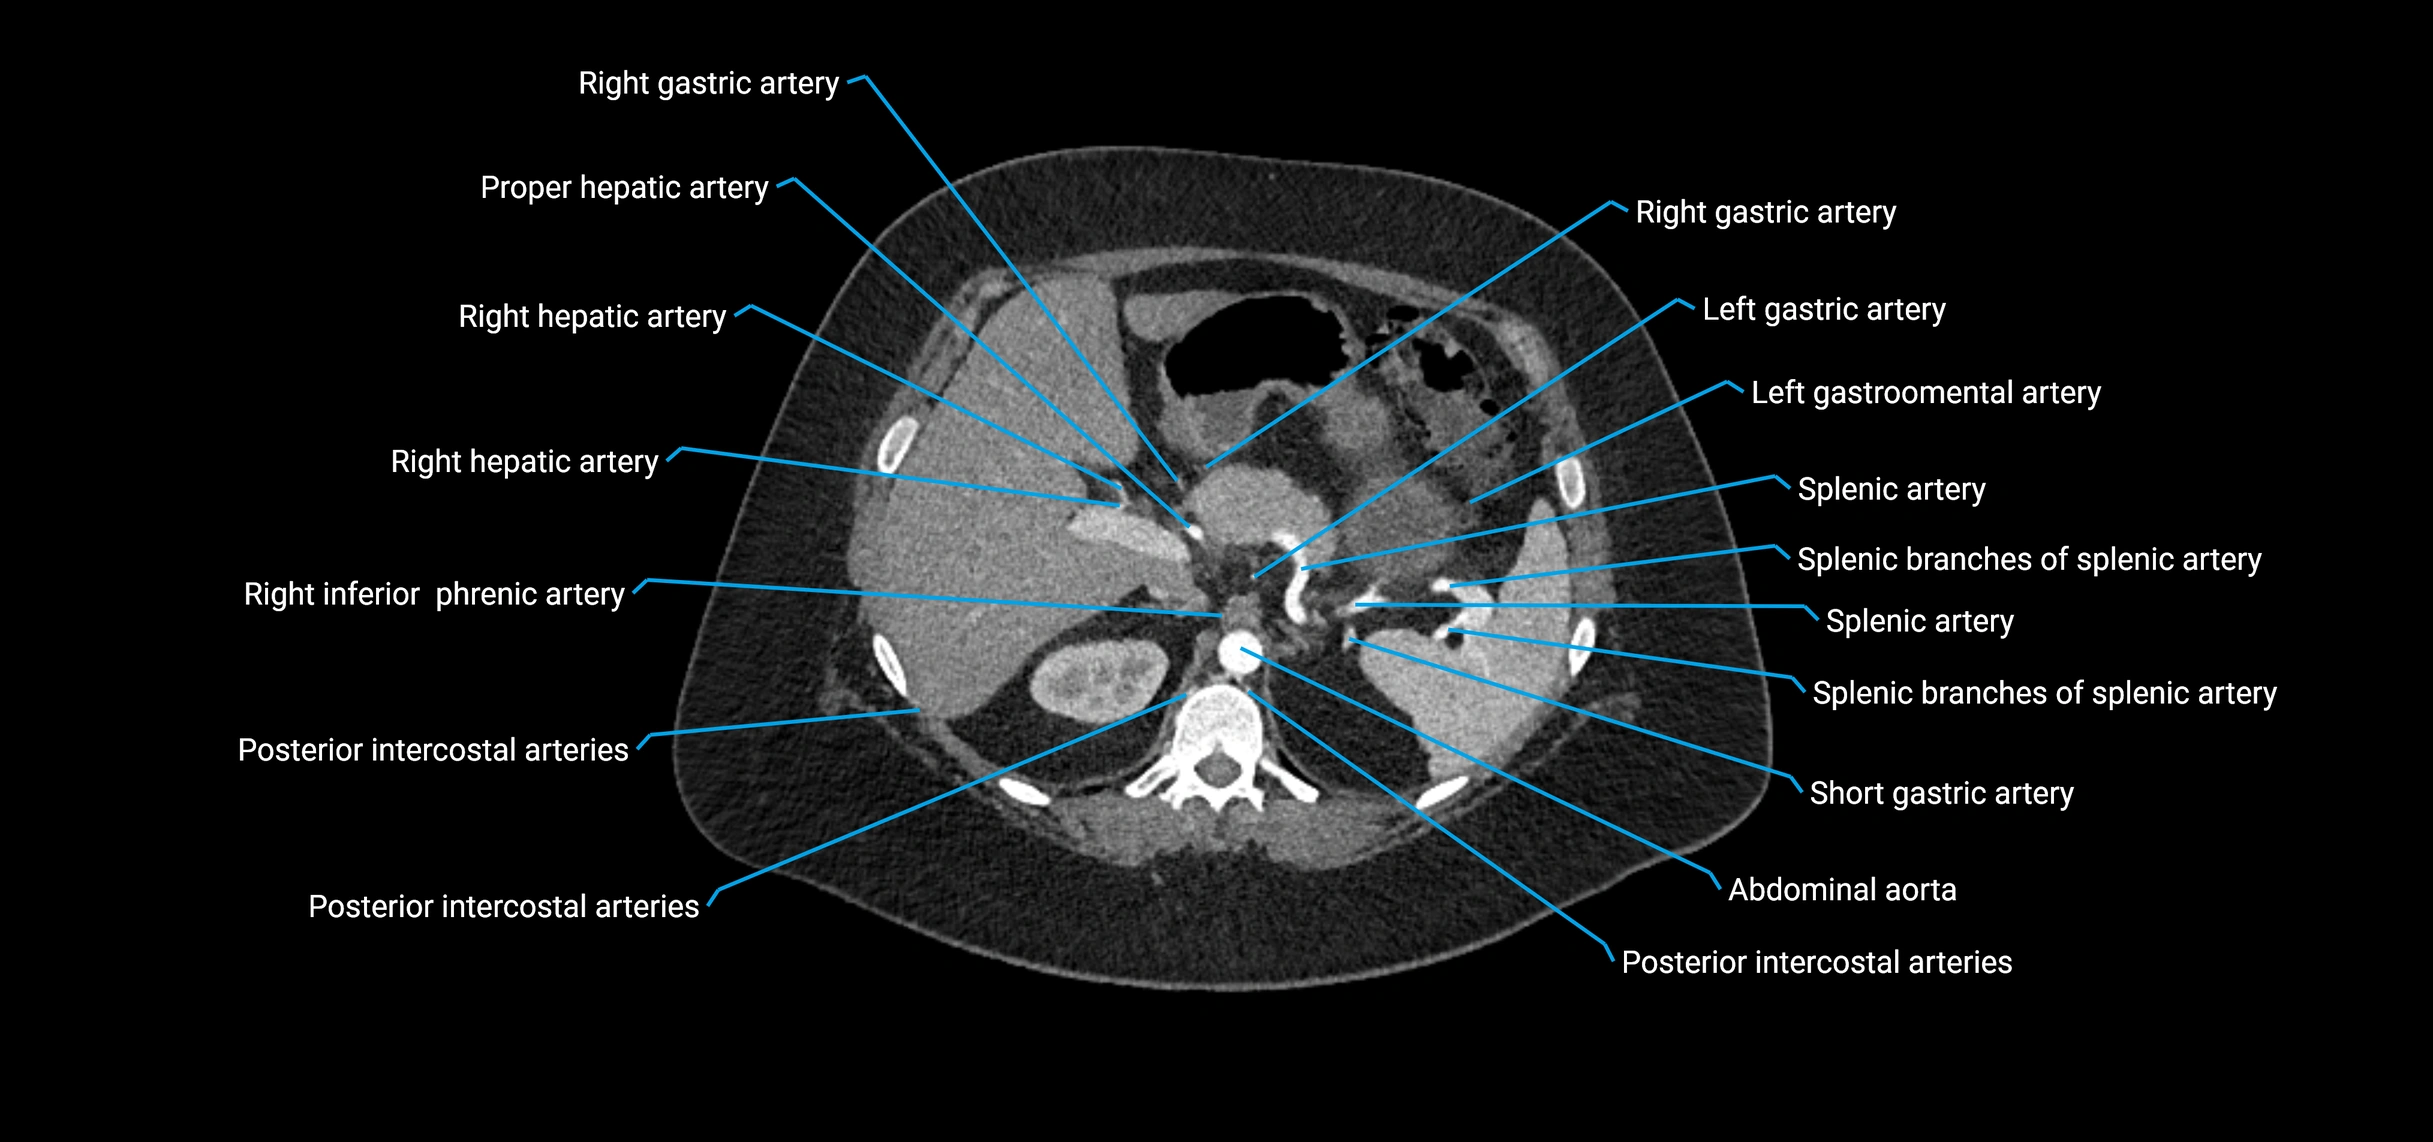

CT Appearance

Non-contrast CT:

• Appears as a tubular soft tissue structure anterior to vertebral bodies

• Calcified atherosclerotic plaques appear as hyperdense foci along the wall

• Useful for screening abdominal aortic aneurysm (AAA) size and mural calcification

Contrast-enhanced CT (CTA):

• Gold standard for abdominal aortic imaging

• Provides excellent detail of lumen, wall, aneurysm, thrombus, and branch vessels

• Multiplanar and 3D reconstructions help in aneurysm measurement, stent graft planning, and dissection evaluation

• Detects acute rupture, traumatic injury, or occlusion with high sensitivity

CT images

image